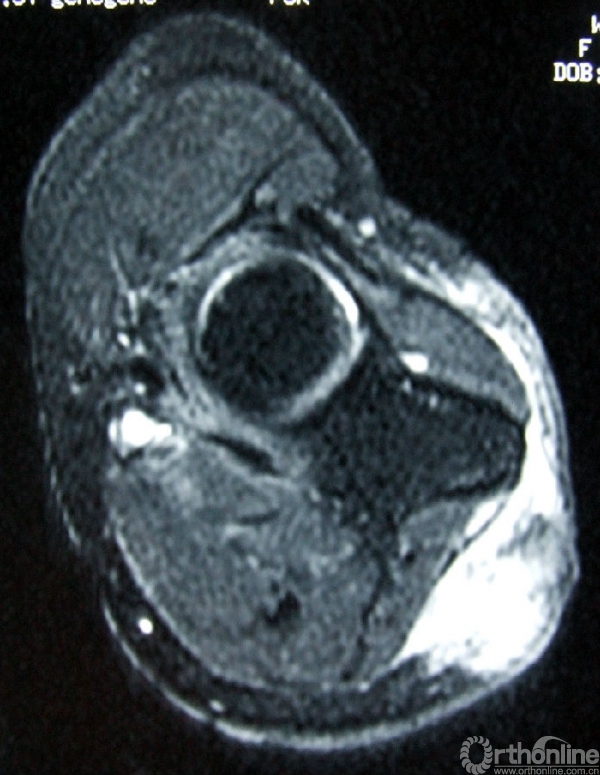

3.辅助检查:化验检查未见明显异常。B超显示右肘关节后方软组织内可见实性杂乱回声包块,1.5cm×1.0cm,界欠清,其内回声不均,可见少许血流信号。手术切口上端深处紧贴尺骨可见低回声小包块,0.9cm×0.2cm,未见血流信号。MRI(图2)示右肘关节后方皮下组织内可见软组织肿块影,边界不甚清楚,T1加权像呈现低信号,T2加权像呈中高信号,增强后T1加权像呈高信号,抑脂像亦呈现高信号。会诊病理(图3)显示成片较密集的轻度-中度间变的短梭形细胞,纤维性间质局部粘液变。初步考虑梭形细胞肉瘤Ⅱ级,可符合恶性外周神经鞘瘤形态。

图2a:T1加权像

图2b:增强后T1加权像

图2c:T2加权像

图2d:抑脂像